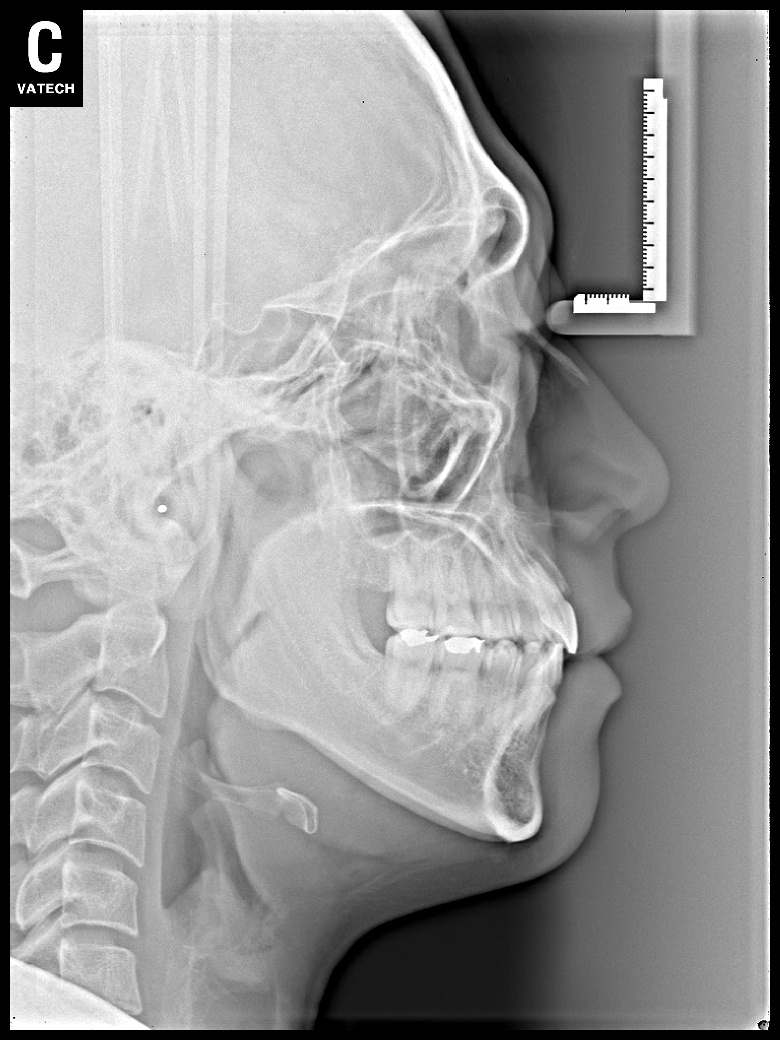

치료 후 사진입니다.